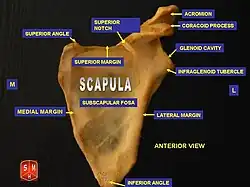

The suprascapular notch (or scapular notch) is a notch in the superior border of the scapula, just medial to the base of the coracoid process.[1] It is converted into the suprascapular canal by the suprascapular ligament.[2]

Structure

This notch is converted into a foramen by the suprascapular ligament, and serves for the passage of the suprascapular nerve.[2] The suprascapular vessels vary in number as well as in their course as they run at the suprascapular notch site. The suprascapular artery pass above the suprascapular ligament in most cases. The suprascapular vein may pass through the suprascapular notch or it may instead pass superior to the suprascapular ligament.[3][1]